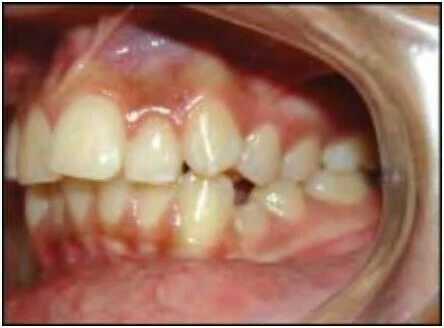

1.7 RĂNG XOAY

Đây là tình trạng những răng di chuyển xung quanh trục dọc của nó. Có hai kiểu xoay răng:

Gần trong hoặc xa ngoài

Mặt gần của răng nghiêng vào trong, hay nói cách khác mặt xa của thân răng nằm về phía ngoài so với mặt gần.

Xa trong hoặc gần ngoài

Mặt xa của răng nghiêng vào trong, hay nói cách khác mặt gần của thân răng nằm về phía ngoài so với mặt xa của nó.